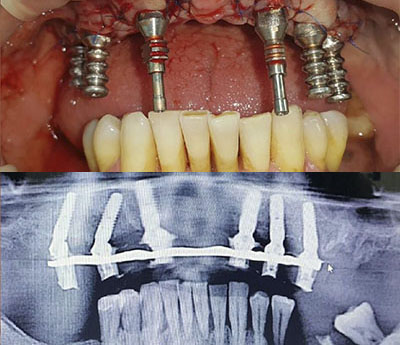

Il sistema Fast&Fixed è un'alternativa immediata. Questa procedura ti permetterà di ritrovare il tuo sorriso in un unico intervento. Il risultato è immediato e recupererai autostima e fiducia in te stesso.